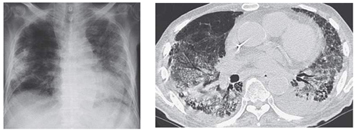

CXR PA

定期受診時(2010.05.10)Baseline

初診時(2010.05.19)

初診5日後 (2010.05.24)

(2010.06.11)背景肺に軽度の肺気腫+間質性肺炎像

(2010.07.18)縦隔リンパ節腫大

胸部CT

両肺に数少ないが多発結節(小葉との関係は判断困難)の出現、出現速度は速く、増大経過(LVFX抵抗性)

2010.05.27 抗生剤( LVFX )投与開始後 解熱なし

2010.06.2) 初診から5週後

増大したものの一部に空洞形成、左上区の最大のものの空洞内には同心円状・索状構造がみられる